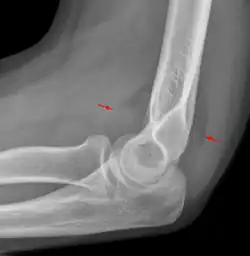

Fat pad sign

The fat pad sign, also known as the sail sign, is a potential finding on elbow radiography which suggests a fracture of one or more bones at the elbow. It may indicate an occult fracture that is not directly visible. Its name derives from the fact that it has the shape of a spinnaker (sail).[1] It is caused by displacement of the fat pad around the elbow joint. Both anterior and posterior fat pad signs exist, and both can be found on the same X-ray.

The fat pad sign is invaluable in assessing for the presence of an intra-articular fracture of the elbow. An anterior fat pad is often normal. However a posterior fat pad seen on a lateral x-ray of the elbow is always abnormal. The patient will be unable to flex their elbow and requires orthopaedic input.[2]